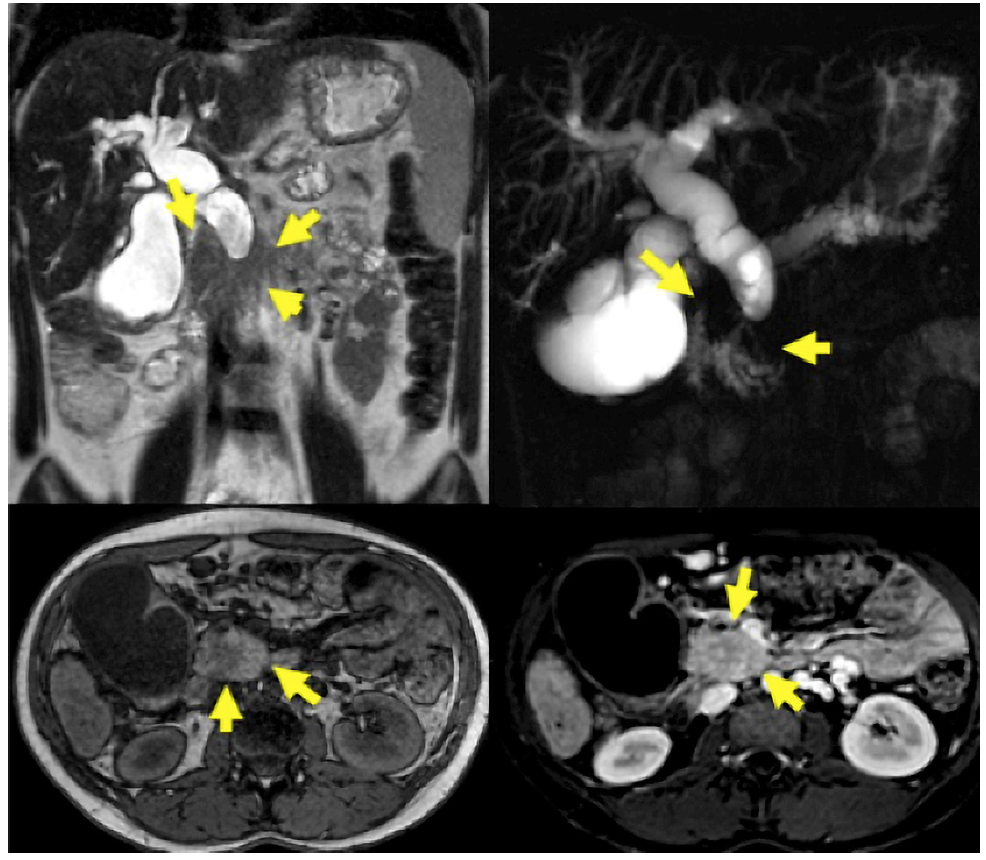

MRI/MRCP was performed on 48 patients. PDAC was suspected in 14 (29.16%), SPN in 14 (29.16%), pancreatic cystic lesion in 7 (14.56%), pancreatic pseudocyst in 4 (8.34%), NF-NET in 4 (8.34%), SCA in 2 (4.16%), chronic pancreatitis in 1 (2.08%), choledochal dilation in 1 (2.08%), and normal in 1 (2.08%) case (Fig. 3). The combination of MRI/MRCP + EUS and MRI/MRCP + EUS-FNA significantly increased (p < 0.005) the diagnosis compared to isolated MRI/MRCP, which went from 29.16% to 66.66% and 94.11%, respectively (Table 4). The sensitivity, specificity, positive and negative predictive value, and accuracy for the SPN diagnosis obtained by MRI was 31.2%, 66.7%, 93.3%, 6.1%, and 33.3%, respectively.

Fig. 3 A 23-year-old woman with signs of chronic pancreatitis on MRI/MRCP and an enlarged pancreatic head.